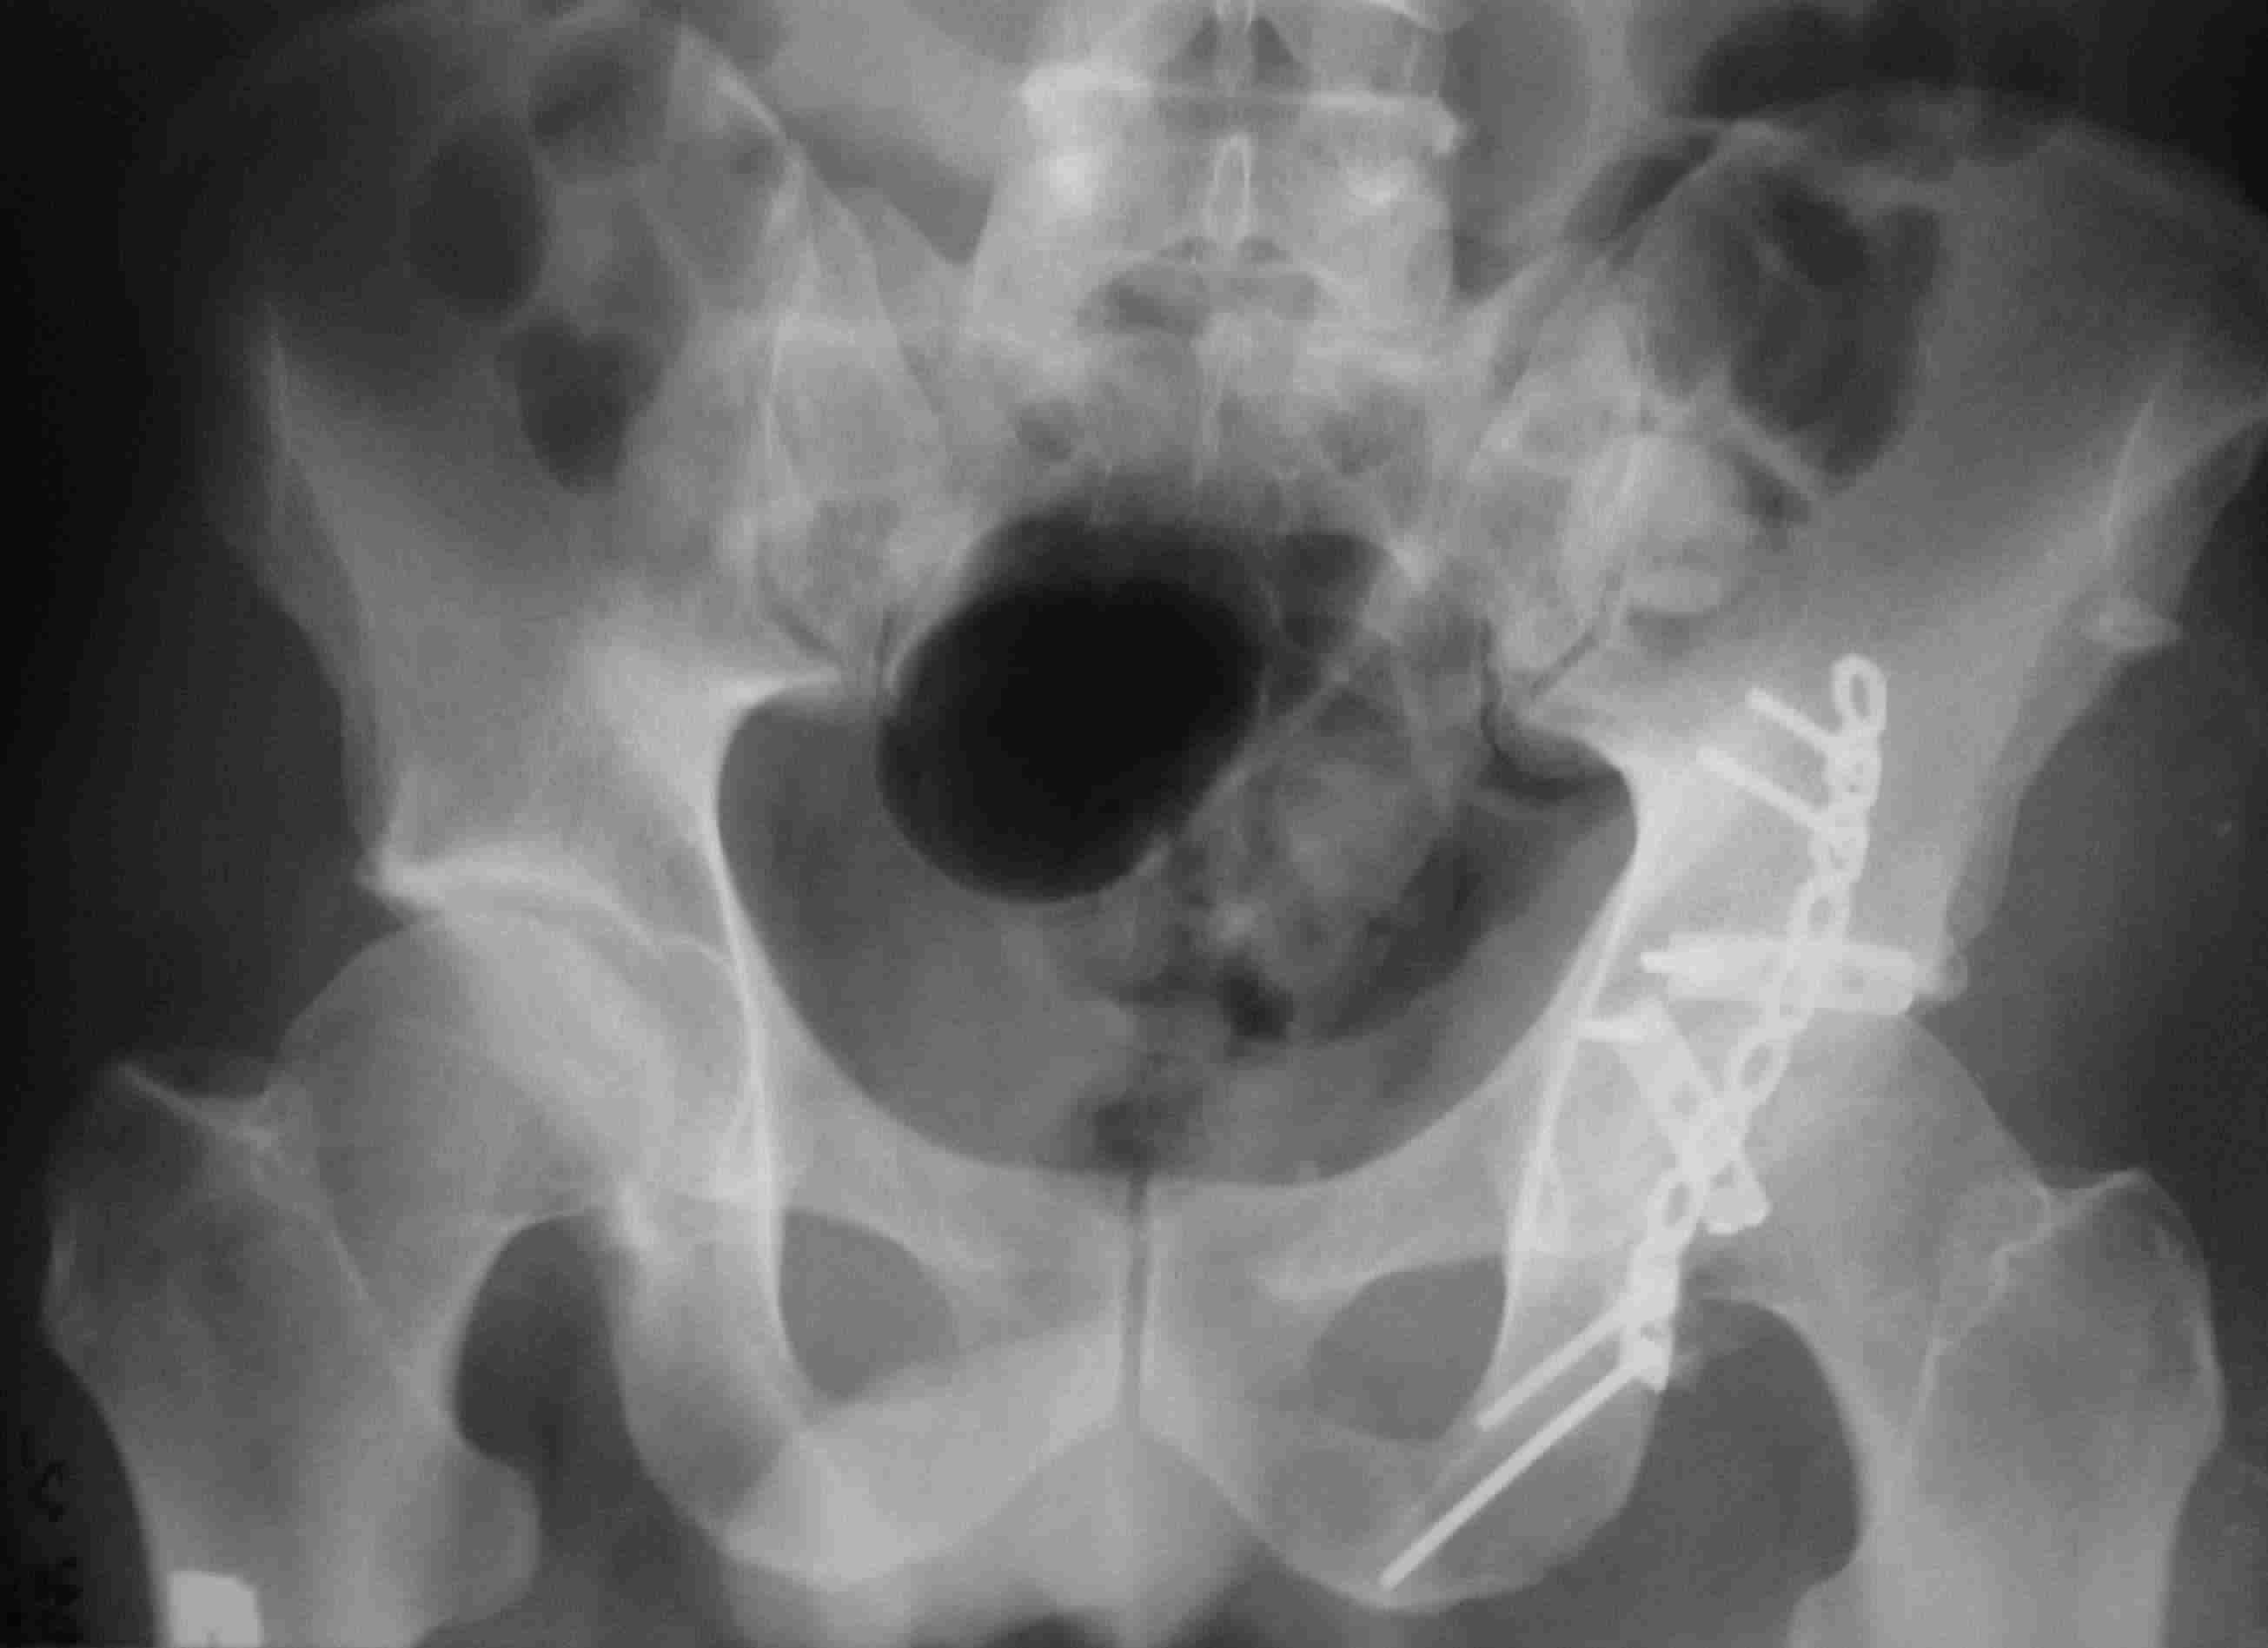

Re: перелом проксимальной тибии + вывих бедра

Серия КТ сканов в аппарате